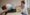

A comprehensive physical examination is an essential part of the diagnostic process. Physiotherapists will evaluate the affected joints, assess the range of motion, and look for signs of inflammation or deformity. They may also perform specific tests to help identify the type of arthritis, such as osteoarthritis or rheumatoid arthritis.

Once a diagnosis of arthritis has been confirmed, physiotherapy can play a crucial role in managing the condition and improving the patient’s quality of life. At Perfect Balance Clinic, our physiotherapists develop customised treatment plans for individuals with arthritis, focusing on pain relief, joint mobility, and overall function.